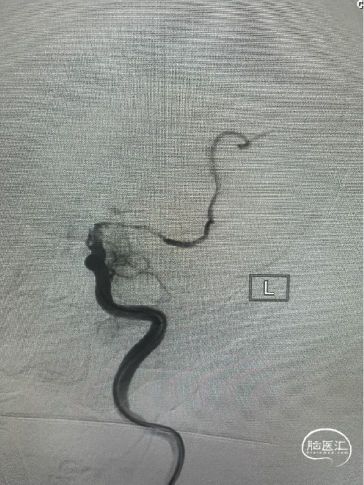

Trevo 6mm×25mm支架释放:

Trevo 6mm×25mm支架释放,全程显影,正位造影提示支架打开。

SWIM技术取栓:

SWIM取栓后,血管再通,无栓子逃逸,闭塞局部无血管狭窄。